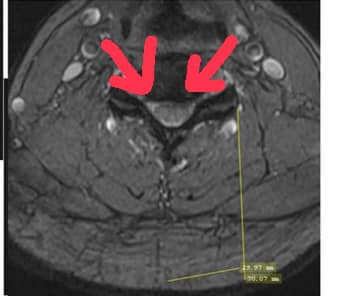

✅MRI cervical radiculopathy

C4/C5;C5/C6左側神經根卡壓

✅thoracic outlet syndrome (胸廓出口症候群)